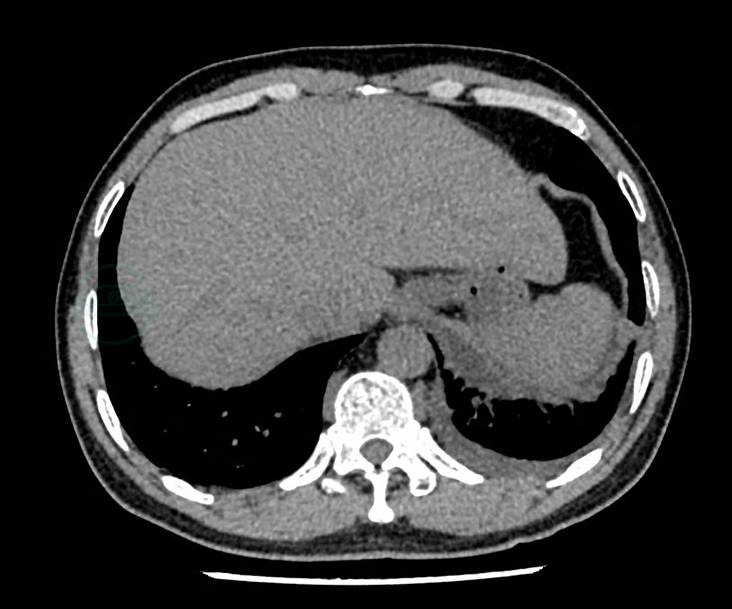

10.肺部CT 支气管炎、双侧胸膜粘连,双侧少量胸腔积液(图1)。

图1 肺部CT